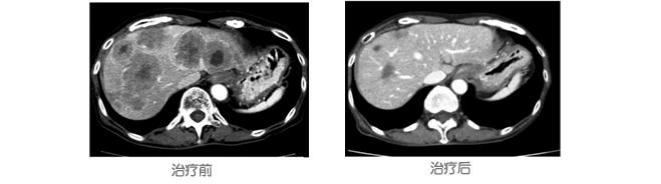

二、基因疗法

2012年10月,71岁,女性,食道癌肝转移,化疗后觉得四肢无力。通过日本多学科专家会诊后,建议她做基因治疗。接受了“超级NK细胞”与“特殊树状细胞”相结合的基因治疗后,使肝脏肿瘤奇迹般地变小了。